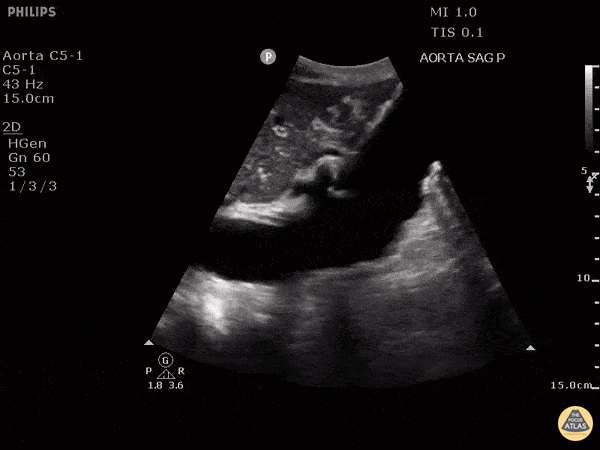

Aorta - Sagittal View of Abdominal Aortic Aneurysm

Sagittal view of large abdominal aortic aneurysm incidentally found after accidental fall. Image courtesy of Robert Jones DO, FACEP @RJonesSonoEM Director, Emergency Ultrasound; MetroHealth Medical Center; Professor, Case Western Reserve Medical School, Cleveland, OH View his original post here